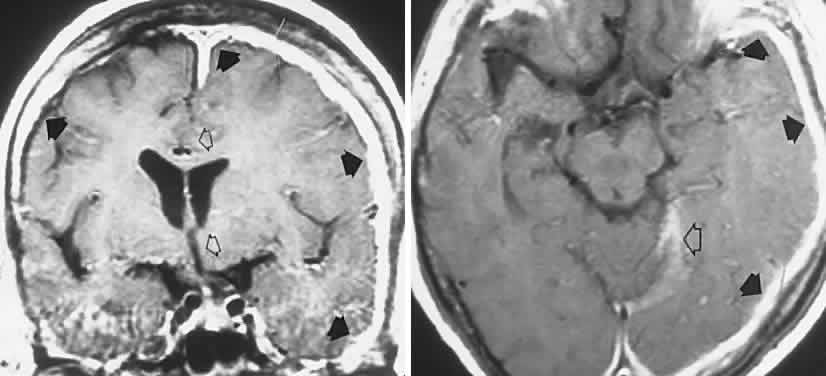

Other subsets of pigmentary retinopathies are due to mitochondrial DNA mutations and are associated with migraine, ataxia, dementia, and Leigh's disease17; the sporadic or maternally inherited MELAS syndrome of mitochondrial myopathy, encephalopathy, lactic acidosis, and stroke-like episodes, usually presents in the teens as cognitive regression, headaches, and cerebral lesions causing field defects.18–20 Even in family members, there is considerable variation of genotypic and phenotypic specificity in metabolic disorders mediated by mitochondrial DNA aberrations, including Kearns-Sayre progressive external ophthalmoplegia (see Volume 2, Chapter 12) and other conglomerations of pigmentary retinopathies. Further identification of gene point mutations will eventually provide a more precise classification.

Progressive cone degenerations present as bilaterally diminished acuity, defective color vision, and aversion to bright lights (photophobia) with “day blindness” (hemeralopia). Central field defects progress, at times showing a fenestrated central scotoma. This widespread loss of cone function usually begins in the first 2 decades of life, but severe cone disease may begin at any age. Heredity is autosomal dominant, but sporadic cases are common, and both severity and rate of progression are variable. The fundus may appear quite normal, a finding that, when coupled with photophobia, provokes an impression of hysteria, but defective pigment epithelium in the form of a “bullseye,” nonspecific mottling, and crystalline deposits are usually enhanced by fluorescein angiography (see also Fig. 1). Mild disc pallor is not unusual. Abnormal single-flash photopic and flicker (i.e., cone-mediated) responses define the disorder by ERG21; fluorescein angiography and full-field ERG may be inconclusive, yet focal ERG is abnormal.22 If considered sooner rather than later, full-field or focal ERG should obviate more exhaustive and inappropriate diagnostic studies for optic nerve disease.